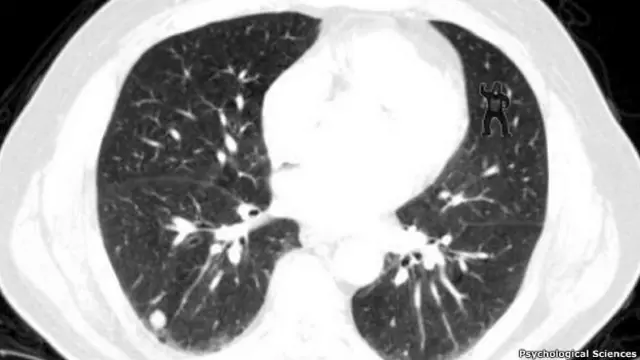

Hay algo extraño en esta tomografía del pulmón de un paciente. ¿Ya lo notó? ¿No vio el gorila bailarín a la derecha?

Pidió a los radiólogos que inspeccionaran tomografías computarizadas de pecho en busca de anomalías, llamadas nódulos, que pudieran indicar cáncer de pulmón. Sin que lo supieran, audazmente superpuso una imagen de un gorila en algunas de las tomografías.

Cuando se les preguntó después si habían visto un gorila, más del 80% de los radiólogos y 100% de los observadores no calificados dijeron no haber visto nada.

Esto, pese a que el monitor de seguimiento de ojos mostró que la mitad de los radiólogos que dijeron no haber visto al gorila realmente lo habían mirado directamente durante medio segundo.